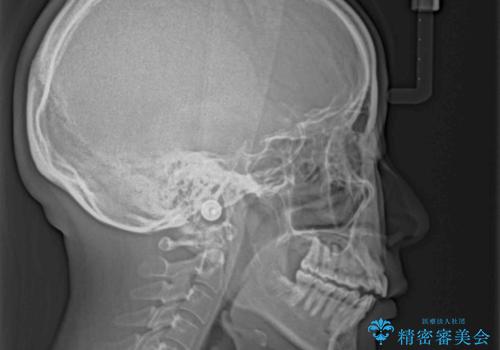

- 前歯の上下スペースによる話しにくさと顎への負担を気にして来院された患者様です。

インビザラインにより上顎の大臼歯を圧下し、上下の前歯の隙間を閉じていくこととしました。

上顎の奥歯を圧下させることで、上下前歯を接触させるように計画しました。